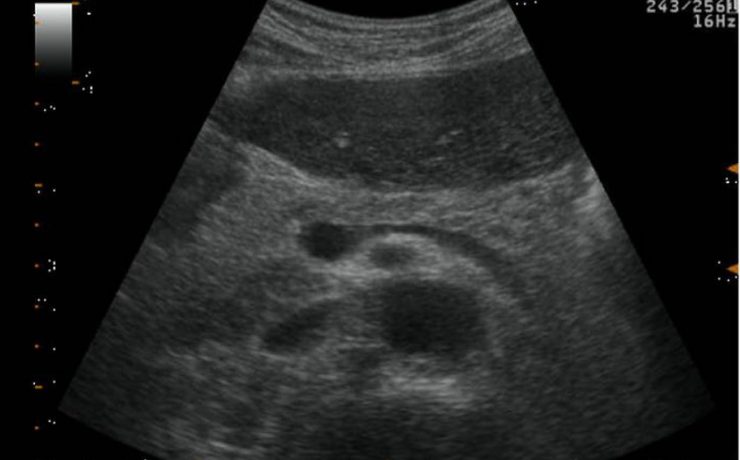

La ecografía transvaginal es el gold-estandar para la evaluación de la patología ginecológica estructura tanto benigna como maligna, con óptimo rendimiento. Actualmente la anatomía patológica funcional no forma parte del estudio ultrasonografico de rutina. Lo que lleva a un sub diagnóstico de patologías frecuentes, como por ejemplo: metrorragias o amenorreas.